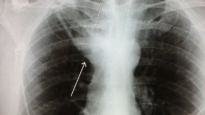

Systematic Interpretation of Shoulder MRI How I do it Mediube Subscribe Subscribed 3 1173 videos 0% 29 Views 0 Likes 2024-12-02 Radiology & ImagingImagingMRI By Mediube 0 Comments (بازدید 29 بار, بازدیدهای امروز 1 ) Show more PREV Rotator Cuff MRI Everything You Need To Know Mediube 2024-11-26 NEXT Abdomen Pelvis CT Pyogenic Liver Abscess Mediube 2025-01-07 You might be interested in 0 Ultrasound Podcast PERICARDIAL TAMPONADE LEARN THIS Mediube 2025-05-12 0 Abdomen Pelvis CT Pyogenic Liver Abscess Mediube 2025-01-07 0 Lobar Pneumonia: Chest X-ray Atlas Mediube 2024-04-06 2 Introduction to CT Chest – Anatomy and Approach Mediube 2024-05-14 0 How To- Ultrasound Guided Paracentesis Procedure 3D Video Mediube 2024-04-21 0 Introduction to Musculoskeletal Imaging Mediube 2025-08-26 Lung Abscess Explanation of Chest X-ray Findings Mediube 2025-01-22 0 Understanding Radiology- What is a Bone Scan? Mediube 2025-09-17 0 MRI Basics Mediube 2024-10-26 0 Imaging of Bones Fractures, Bony Anatomy and Bony Density–Radiology Mediube 2025-09-06 0 Lung Abscess Mediube 2025-01-22 0 Maxillary sinus imaging and sinusitis Mediube 2024-08-24 LEAVE YOUR COMMENT Cancel replyYour email address will not be published. Required fields are marked * Save my name, email, and website in this browser for the next time I comment. Δ